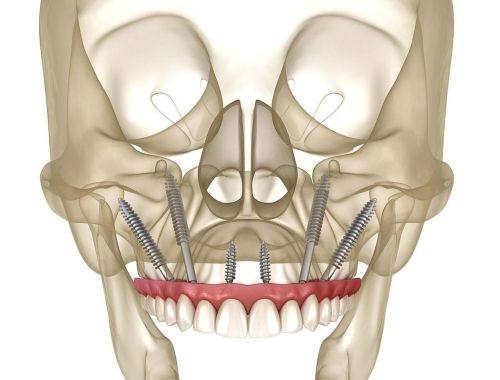

种植牙:主推奥齿泰种植体,可开展all-on4、穿颧穿翼等高难度种植手术,复杂手术通常40分钟左右即可完成

买院长:擅长种植牙领域,可开展all-on4、穿颧穿翼等高难度种植手术,临床经验多